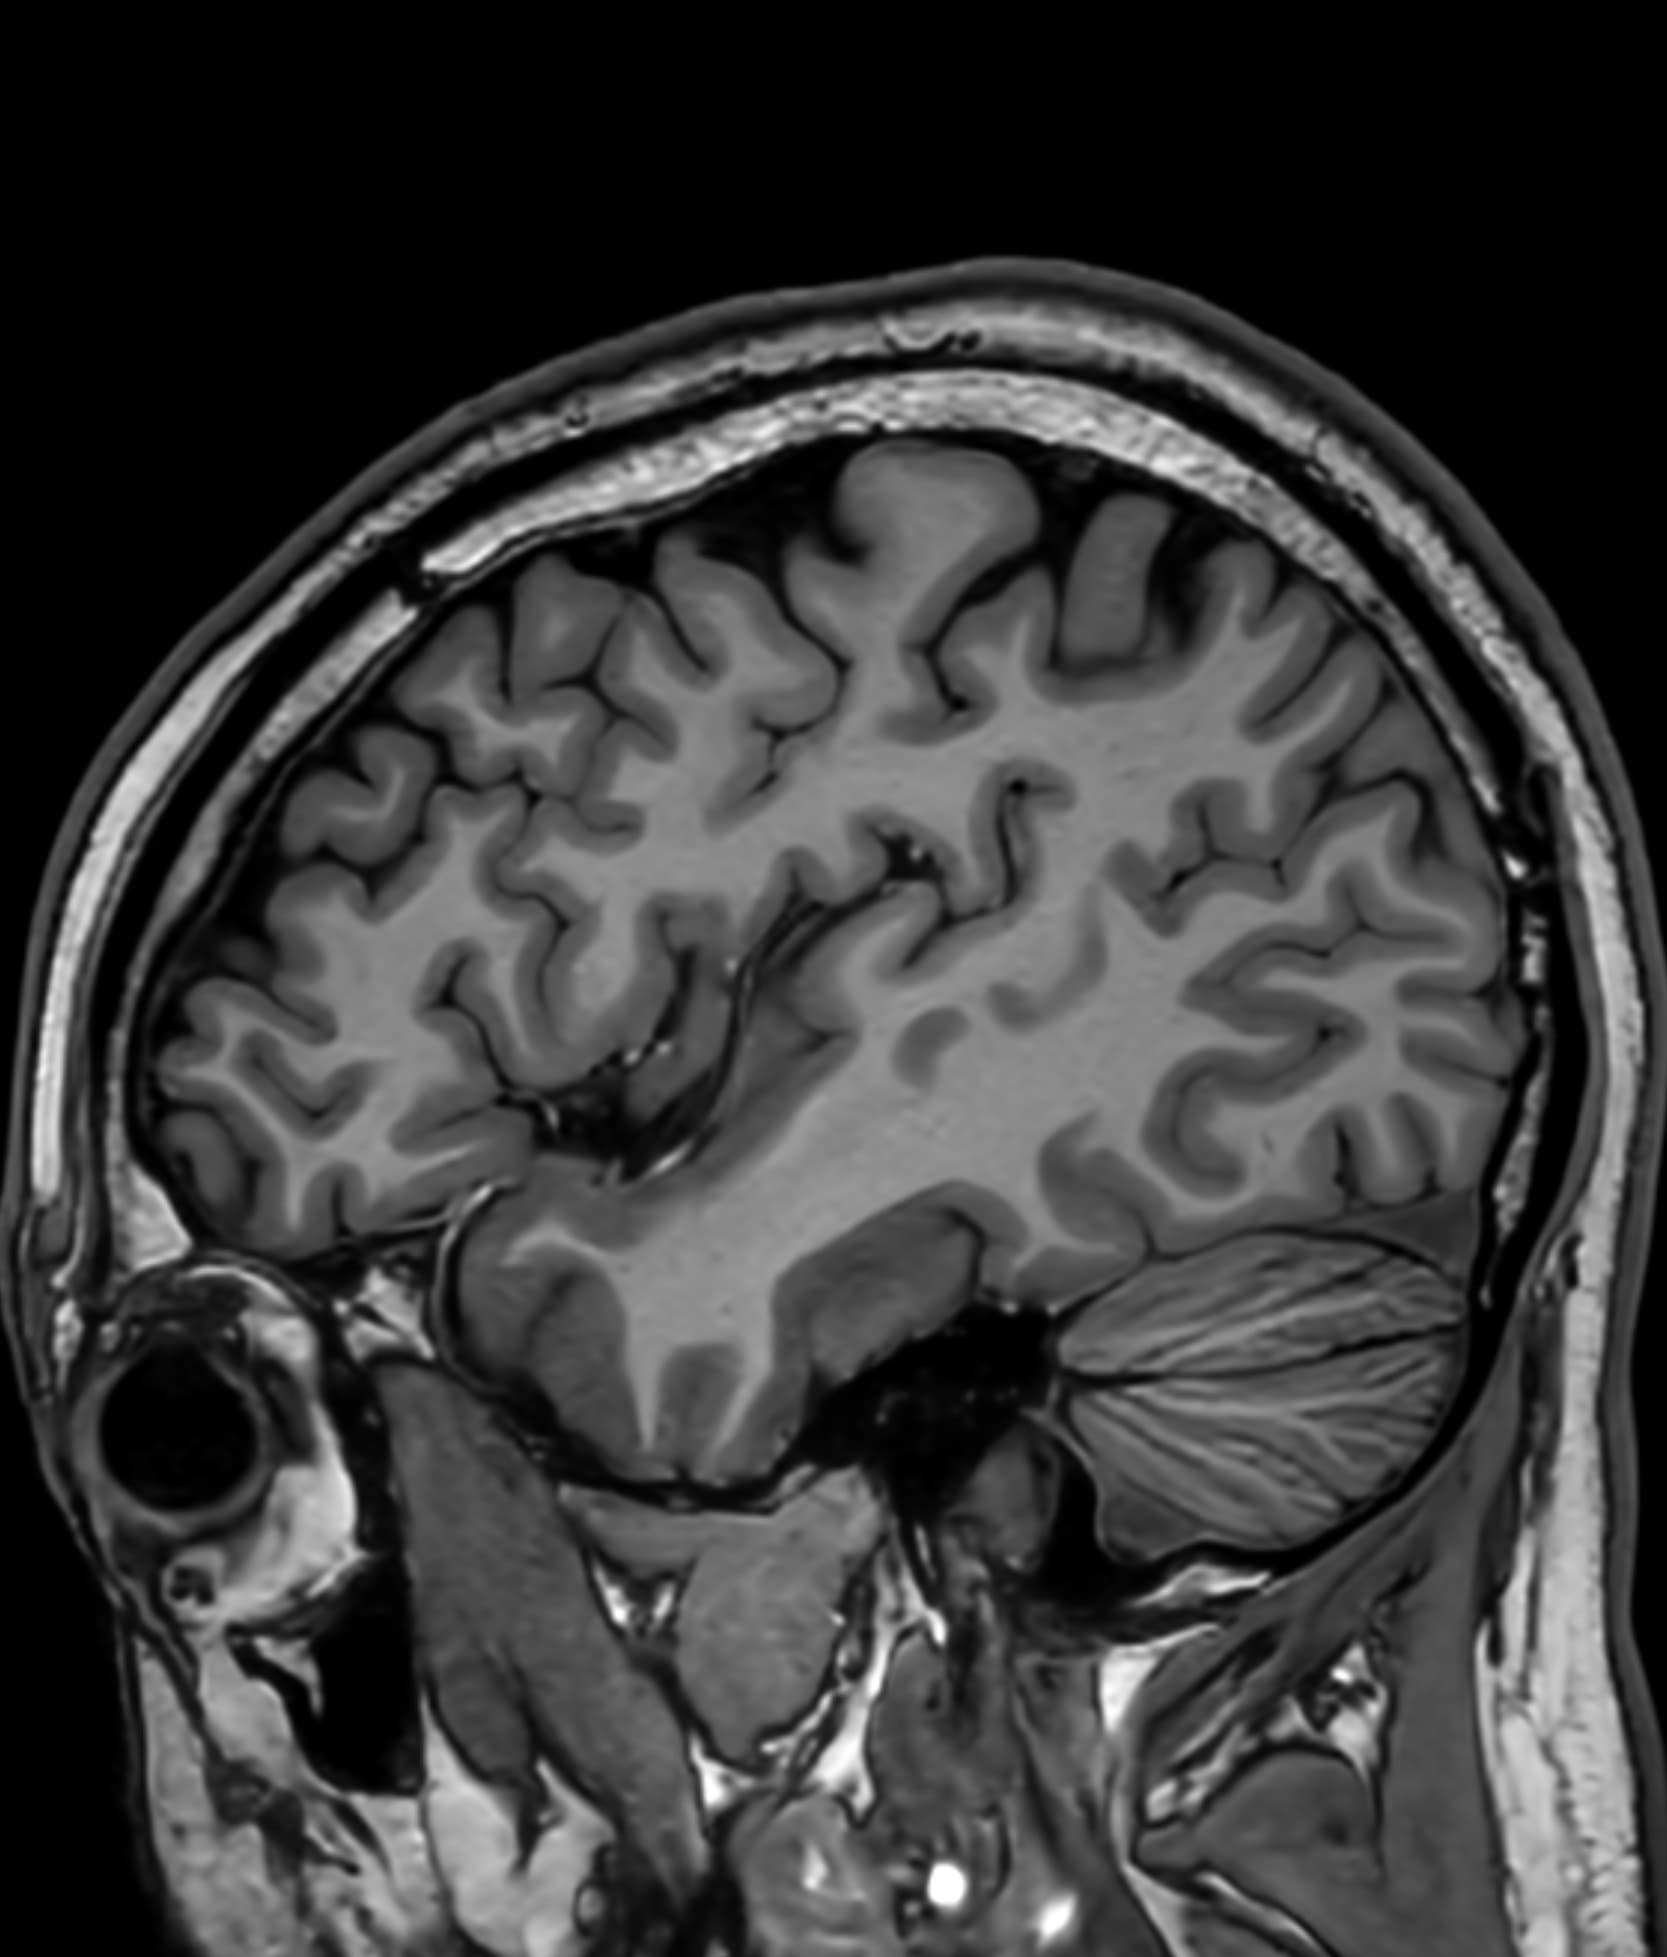

Δείτε πραγματικά παραδείγματα του SwiftMR™ σε διάφορα συστήματα MRI και ανατομικές περιοχές

Scan time 04:53

Scan time 1:46